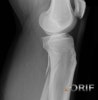

X-ray : 비골 근위부 골절(Proximal fibula fracture)

무릎의 AP & lateral view 외에 oblique view를 시행합니다.

무릎의 불안정성이 발견되거나 의심되면 MRI를 시행합니다.